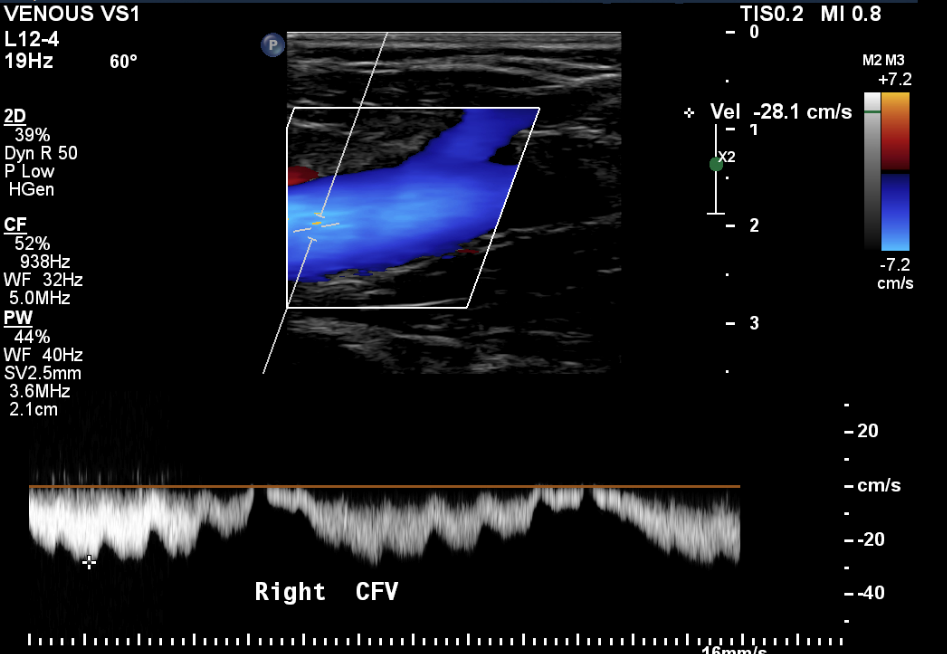

Varicose Veins of the Lower Extremity Doppler US Evaluation Protocols Gold Standard Test For Varicose Veins Turning now to pvr, the gold standard investigation has been shown to be the transvaginal venous duplex ultrasound scan. Randomized clinical trial comparing endovenous laser ablation with surgery for the treatment of primary great saphenous varicose. Phlebography by vein x‑ray using contrast medium was the gold standard for vein diagnosis by imaging for decades. Duplex ultrasound scanning is now the. Gold Standard Test For Varicose Veins.

Figure 1 from Vascular Ultrasound Exam for Varicose Veins . Importance Gold Standard Test For Varicose Veins Randomized clinical trial comparing endovenous laser ablation with surgery for the treatment of primary great saphenous varicose. While open surgery remains the ‘gold standard’, most veins can be treated successfully with a range of options. Phlebography by vein x‑ray using contrast medium was the gold standard for vein diagnosis by imaging for decades. Turning now to pvr, the gold standard. Gold Standard Test For Varicose Veins.